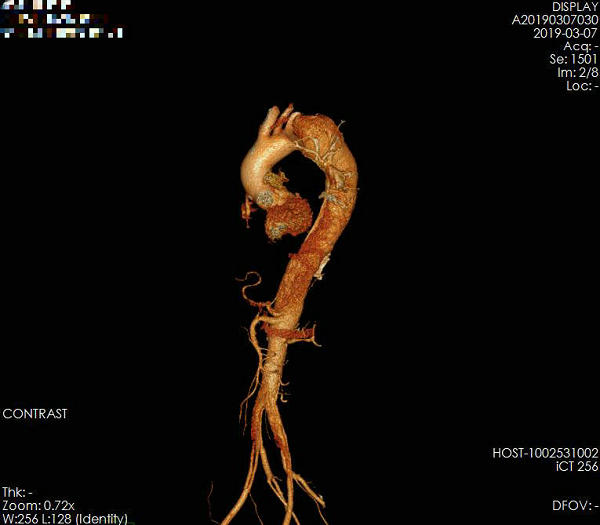

49岁的柴先生有20年的高血压病史,平时用降血压药物,血压控制不理想,近日以“突发胸背部剧烈疼痛3小时”来郑州大学五附院血管外科住院治疗。入院时查体:痛苦面容,心率72次/分,律齐,股动脉动脉搏动可。在血管外科司江涛主治医师接待病人后,迅速完善术前相关检查。胸主动脉CTA检查提示:胸主动脉夹层,DeBakeyⅢ型,破口巨大,假腔向上逆撕至累及左锁骨下动脉及左颈总动脉,主动脉弓上三分支血管距离太近,左椎动脉为优势供血动脉(图1)。

▲ 图1术前CT